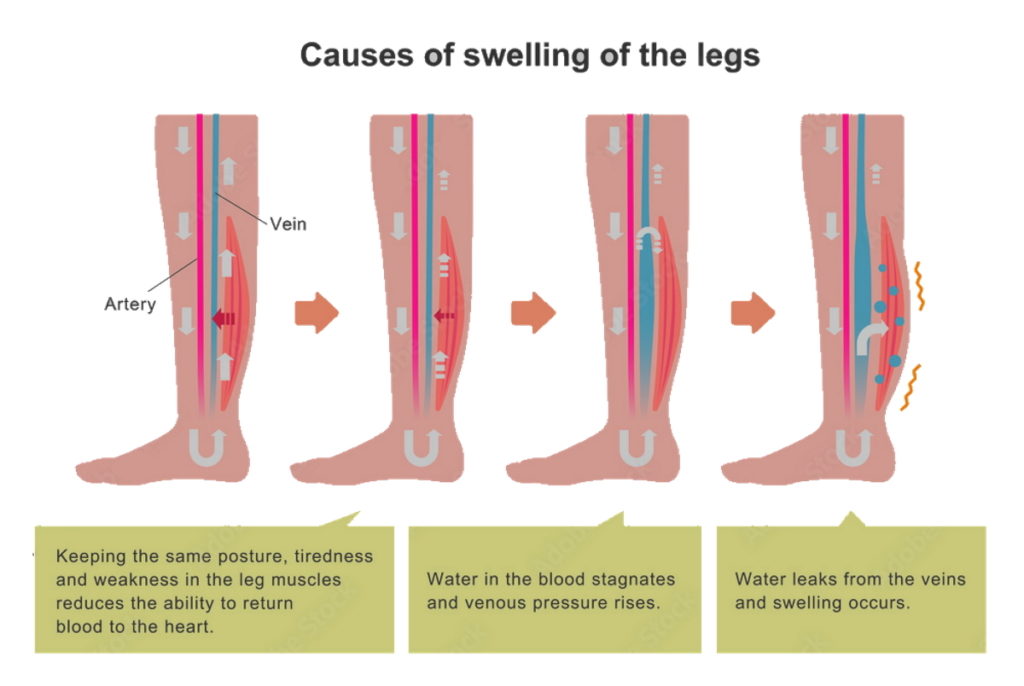

Can Tight Pelvic Floor Cause Edema Viewfloor co

https://www.precisionvir.com/wp-content/uploads/2022/10/edema_illustration-leg-swelling-causes-1024x686.jpg

Water Retention Causes Symptoms And Remedies Possible

https://possible.in/wp-content/uploads/2020/11/cure-water-retention.jpg